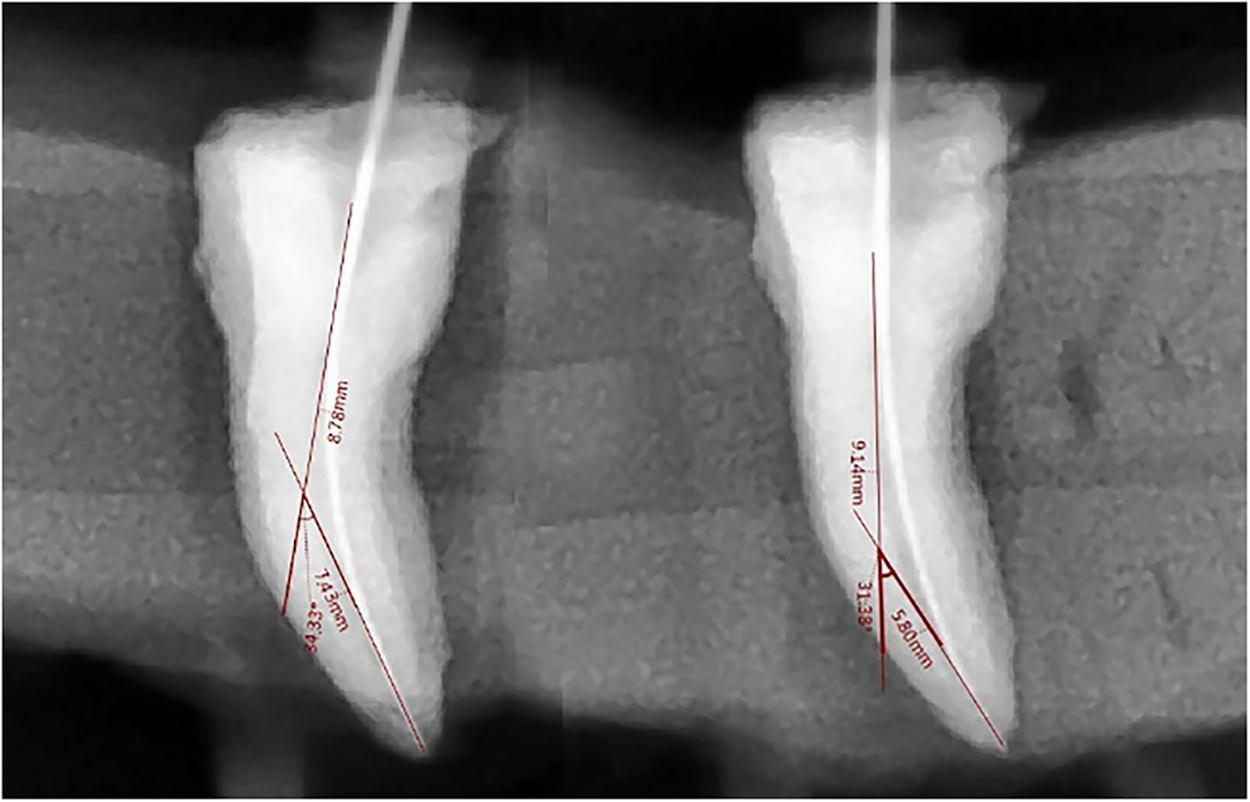

Lastly, sterile paper tips were used to dry the canals. Only the researcher prepared each channel. The following instrumentation, the same circumstances as for initials were used for the specimens to take radiographs using digital dental periapical imaging (Figs. 1–3). The identical method as previously described was used to take the post-operative photos. The same procedure was used to measure the specimens’ canal curvatures. The initial measurement was of the post-instrument canal curvature.

Fig. 3. Pre- and post-instrument curvature change in group C.